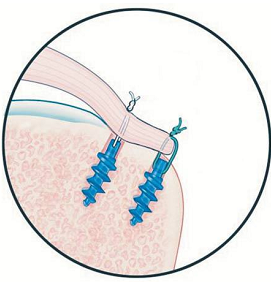

8. O que é uma âncora no ombro?

Muitos pacientes perguntam isso.

Âncora é um pequeno dispositivo (geralmente de titânio ou material absorvível) usado para fixar o tendão de volta ao osso.

Ela funciona assim:

- uma parte vai presa ao osso

- fios saem da âncora

- esses fios costuram o tendão

- o tendão é reinserido na posição correta

📌 Não trava movimento.

📌 A maioria é absorvível com o tempo